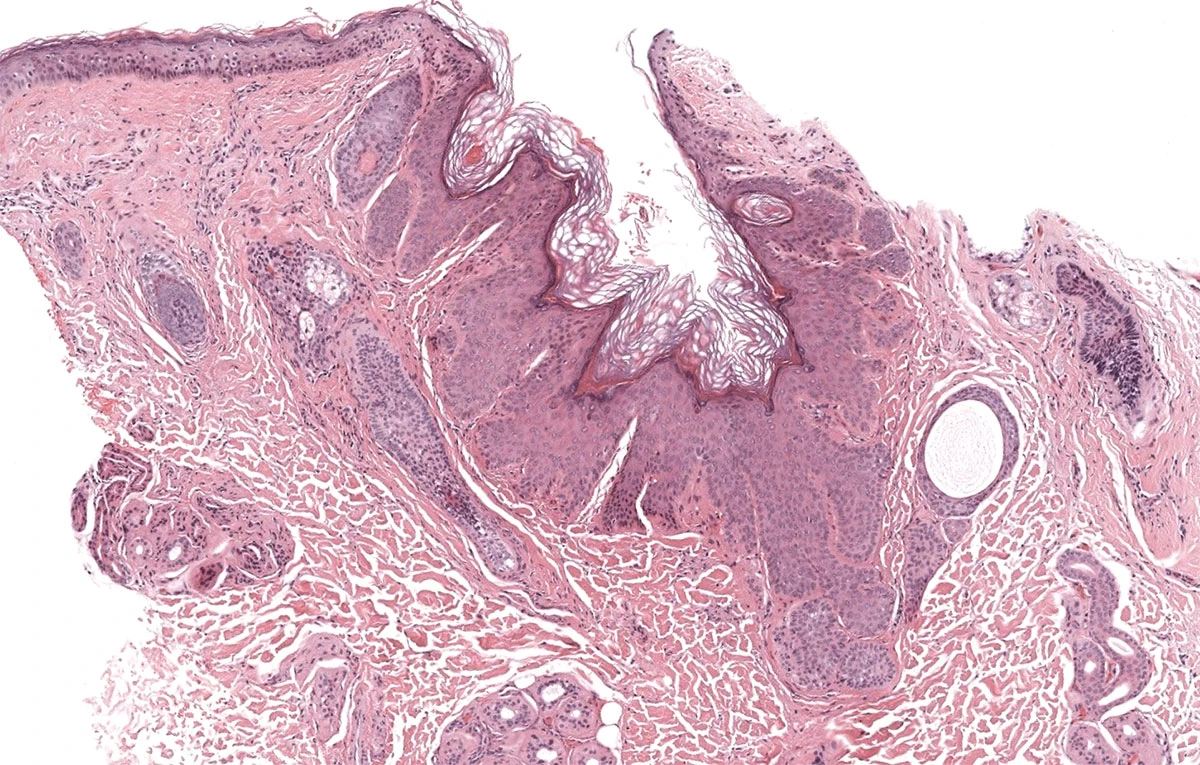

- Módulo 2: Patrón psoriasiforme